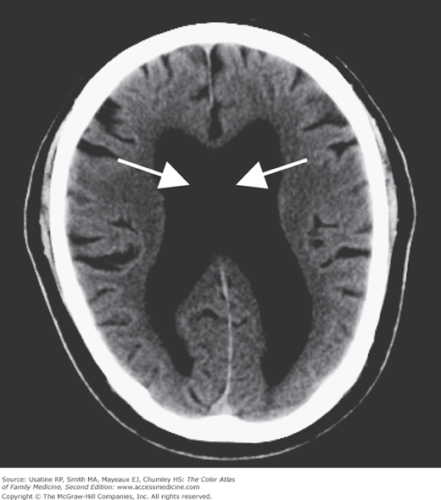

Recognizing normal pressure hydrocephalus in older adults : Nursing2022

21 – Normal pressure hydrocephalus syndrome secondary to hemorrhage …

Normal pressure hydrocephalus | Image | Radiopaedia.org

Diagnosis and Treatment of Adult Hydrocephalus | Neupsy Key

Normal pressure hydrocephalus | Image | Radiopaedia.org

Normal pressure hydrocephalus | Image | Radiopaedia.org

Normal pressure hydrocephalus | Image | Radiopaedia.org

Normal pressure hydrocephalus – Cancer Therapy Advisor